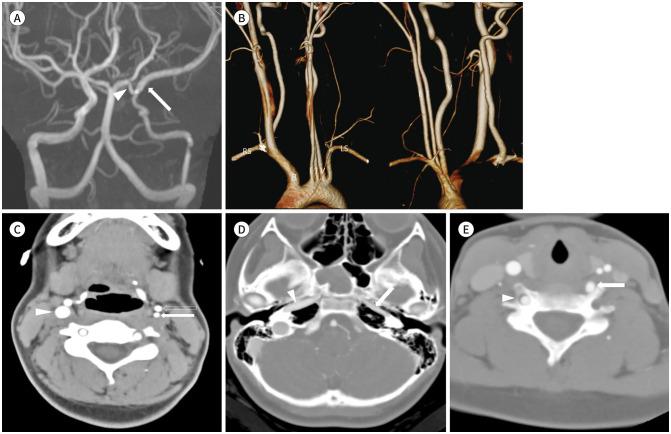

Combined Anatomical Anomalies of Direct Aortic Arch Origins of the Left Internal Carotid, Left External Carotid, and Left Vertebral Arteries: A Case Report.

Various branch anomalies of the aortic arch have been reported, but cases with separate origins of the internal and external carotid arteries with combined direct aortic arch origin of the left vertebral artery are extremely rare. Herein, we present a rare case of aplasia of the left common carotid artery with separate origins of the ipsilateral internal and external carotid arteries and vertebral artery from the aortic arch in a 10-year-old girl. In addition, we review the embryological development and clinical implications of these anatomical variations.